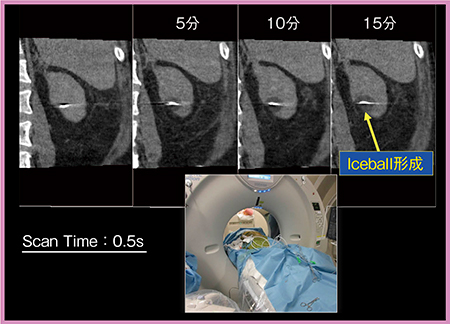

2011年5月,小径腎がん(RCC)に対する凍結療法が保険適用となった。当院では320列の最新型Angio CTと同時に冷凍手術器を導入し,2017年4月から実際に小径RCCに対する凍結療法を開始した。

モニタリングのため,凍結中には適宜,320列ADCTのVolume One Shotモードで撮影する(図6)。Volume One Shotでは,1回転0.5秒で160mm幅を撮影できるため,寝台や被検者を動かすことなく広範囲の穿刺状態を確認できる。Volume One Shotでは,撮影後に方向を変えたオブリーク画像も作成することができるため,手技を安全かつ迅速に進めることができる点で大変有用なツールである。今後はさらなるリアルタイム性の向上に期待している。

図6 凍結療法におけるVolume One Shotでのモニタリング